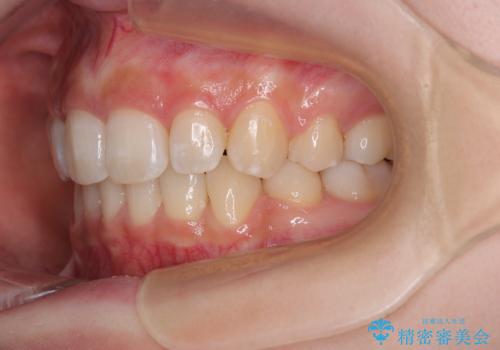

抜歯矯正により、下唇が前方に突出した感覚が大幅に改善されました。

- 上顎前歯の突出感を気にして来院された患者様です。

上下左右第一小臼歯4本を抜歯して、積極的に口元を引っ込めるよう、ワイヤー装置にて矯正治療を行うこととしました。